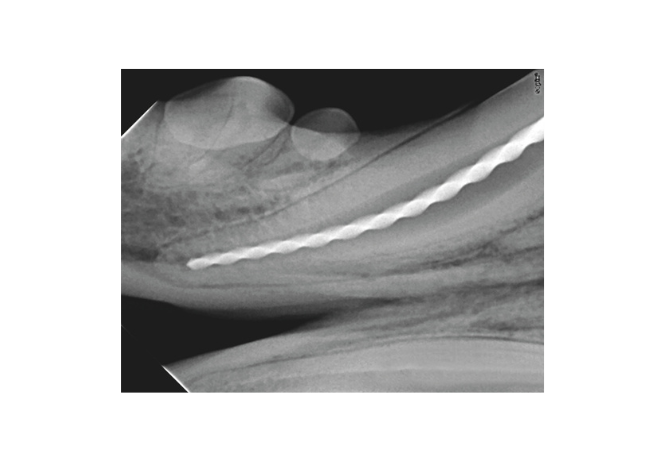

Intelligent digital sensor guarantees high-resolution images. Equipped with Ace® technology, the Sopix®² sensor ensures image reliability for fast, reliable diagnosis.

The Ace® technology protects the image from overexposure for optimal quality without any effort.

Sopix® Series visually differentiates dental tissues and provides a reliable image of the tooth anatomy, guaranteeing safe and rapid diagnosis.